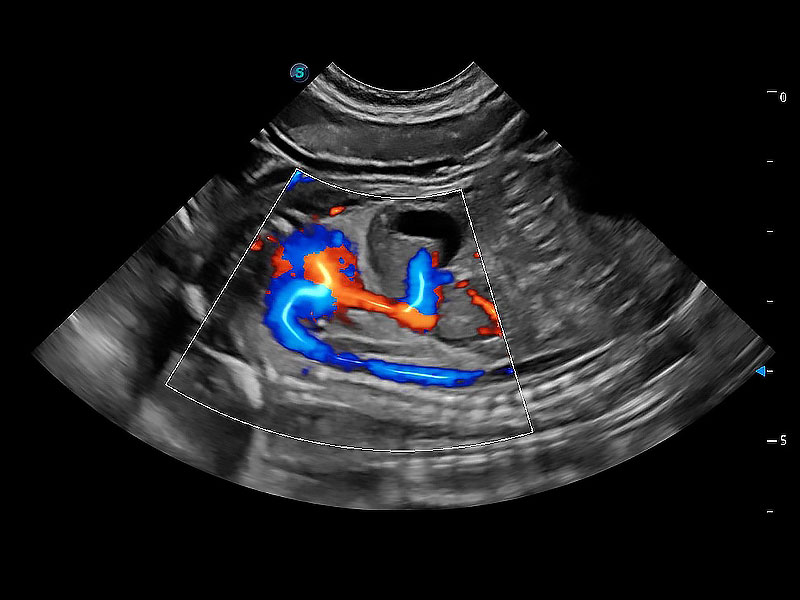

极大提升超低速微细血流的检出能力,同时更精准地滤除软组织和超声信号,为兽用医生提供以往无法通过常规血流获得的疾病诊断信息。

在传统二维血流成像的基础上,呈现血流的立体感,具有动感的生命力之美。即便是微小的血管也能轻松应对,提高了血流的视觉敏感性。

非线性融合造影成像充分利用谐波和基波信号,为难以观察的血流进行增强显像。可用于线阵、凸阵、微凸阵、相控阵探头。